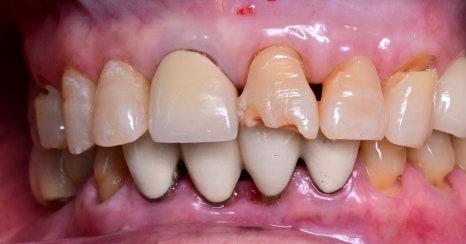

Right photo: An intraoral photo of the patient’s front teeth.

The front teeth were broken and there were also old prosthetics, so both esthetics and function needed to be restored.